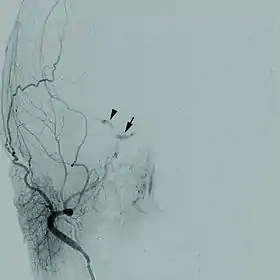

Цереброваскулярні хвороби

Цереброваскулярні захворювання належать до найбільш розповсюджених неінфекційних хвороб і найчастіших захворювань нервової системи., а їх найнебезпечніша форма — гостре порушення мозкового кровообігу (ГПМК) — зустрічається частіше, ніж гострий інфаркт міокарду[1] Часто інсультам передують короткочасні порушення мозкового кровообігу у формі транзиторної ішемічної атаки. В світі щороку реєструється понад 15 млн інсультів, і майже половина інсультів і третина смертей від інсульту спостерігається у віці молодше 70–75 років. З інсультами пов'язані 10 % всіх смертей (майже 6 млн на рік в світі), проте у більшості випадків наслідком ГПМК є не смерть, а обмеження життєдіяльності.